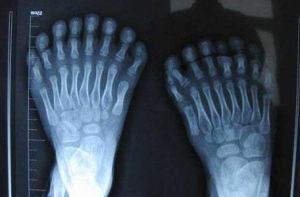

並指的類型包括:單一併指、多指並指、不完全並指、完全並指、單純並指、複雜並指、手套樣並指等。疾病病因

並趾治療

一般宜在3歲以後至學齡前的期間內施行為宜。過早施行手術,術後創口疤痕常會影響手指的正常發育,且手指纖細短小,也不易準確進行手術操作。手術原則

指(趾)間軟組織切開,皮膚Z性延長或缺損傷口全層植皮。手術步驟

術中需特別注意血管與神經的解剖異常,防止誤傷。術後督促患兒的手指功能鍛鍊至關重要。